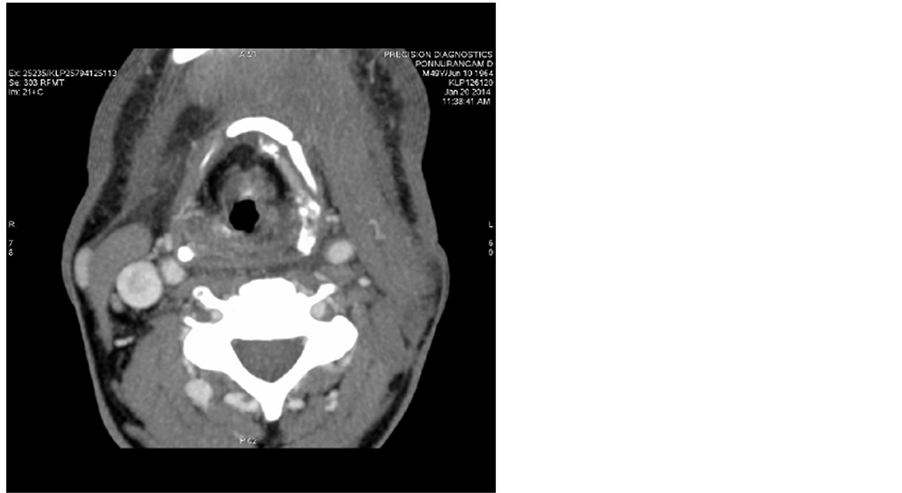

Post treatment CT scans done on 20/01/2014 shows no significant mass (Figure 2) and no lymphadenopathy (Figure 3).

Figure 2. Post treatment CT scans done on 20/01/2014 shows no significant tongue mass.

Figure 3. Post treatment CT scans done on 20/01/2014 shows no lymphadenopathy.

At the end of 1 year no malignant mass was noted on post treatment CT scans with no lymphadenopathy.